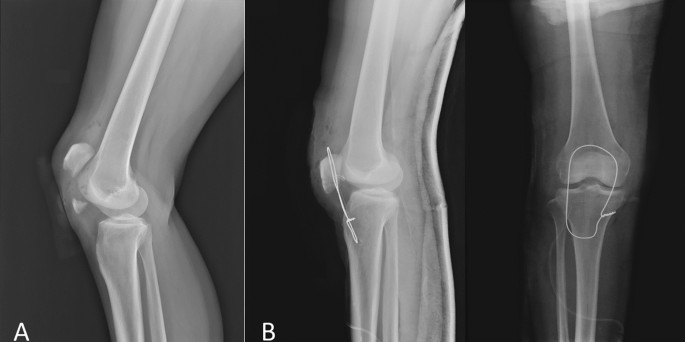

Because of the inability to perform tension band wire fixation, all the patella distal pole fractures were treated with patellar tendon reattachment. Without sacrificing distal bony fragments, obtain the contact of the fractured raw surface during operation. Patella was exposed through a midline longitudinal approach, and the retinaculum was carefully preserved through subcutaneous dissection. After the hematoma was evacuated, the fracture site was exposed. The distal patellar pole fragment was preserved as much as we can unless it was too comminuted to have the risk of becoming loose bodies in the joint or has already become free bony fragment as the devitalized debris. The capsulotomy was not performed because the articular surface was not involved so that it is not required to confirm the reduction of the articulation. Therefore, most of the patella bone blood perfusion was not compromised. Two No. 5 Ethibond sutures used for repair were woven through the medial and lateral halves of the inferior patella pole and patellar tendon with the Krackow technique (Fig. 1). Kirschner wire (2.0 mm or 2.5 mm) was used to drill three longitudinal tunnels through the upper part of the patella from the fracture surface. The four ends of the Ethibond suture were passed through the drilled tunnel and tied firmly over the intact edge of the patella upper pole with the knee in full extension (Fig. 2). After that, No. 1 absorbable Vicryl suture was used to repair the torn medial and lateral retinaculum. The wire was passed transversely through both the tibial tuberosity and the upper patella as a loop for the group with augmentation wire use. Then, the wire was twisted and tightened, while the knee was kept at 90° flexion to resist the power that would make the reattachment separate (Fig. 3).